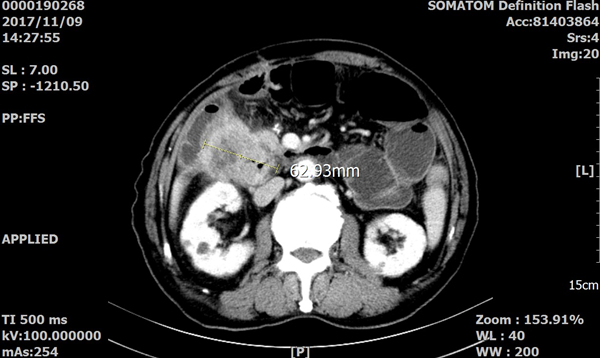

患者9个月前因肠梗阻在外院就诊时发现升结肠癌,术中发现已局部侵犯肝脏及十二指肠,为避免手术风险过大,仅行右半结肠切除及部分肝切除术,十二指肠残留部分肿瘤,术后经6个疗程化疗后无明显复发迹象。1个月前患者至北京探亲时再次发生肠梗阻,住院CT发现腹腔内肿块,提示复发可能,经保守治疗无效,当地医生告知患者家属不手术可能仅有数月的预期生命,但再次手术风险太大,已基本没有治疗可能。患者及家属返回西安后来我院干四病区(普外四病区)就诊。

经过积极的术前准备以及与家属的充分沟通,在麻醉科和手术室大力配合下,杨正安主任医师、张澍副主任医师和蒋安副主任医师为患者成功实施了手术。手术共耗时6个多小时,因患者为二次手术,腹腔内广泛粘连,仅分离粘连就用去2个多小时,显露病灶后发现肿瘤直径约7cm,已侵及胰头部、胆管、远端胃、十二指肠及原结肠与回肠吻合部位,已包裹成团,遂行胰十二指肠切除、部分回肠与结肠切除吻合术,将肿瘤完整切除,经病理证实为胰头部肠上皮来源的转移癌,切缘无癌组织残留,未见淋巴结转移。术后杨正安主任医师和张澍副主任医师针对高龄、手术创伤大等特点,给予患者个体化的支持治疗方案,无手术并发症发生。